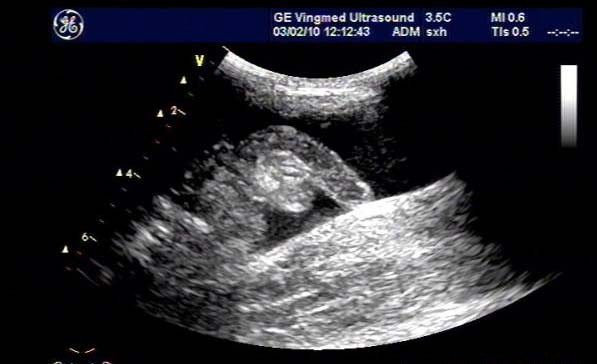

闌尾炎是美國(guó)兒童常見(jiàn)的疾病,發(fā)生率持續(xù)增加;雖然CT是最常用來(lái)評(píng)估疑似闌尾炎患者之癥狀的影像技術(shù),但它與顯著增加放射線暴露有關(guān),而超聲檢查不會(huì)有放射線暴露。

研究目標(biāo)是,兒童急性闌尾炎時(shí),使用超聲檢查作為第一種影像檢查方式時(shí),確認(rèn)是否會(huì)增加復(fù)雜性闌尾炎比率與住院天數(shù)(LOS)。